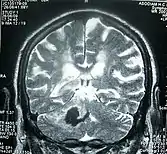

Magnetic Resonance Image of Brain After Stroke

Perinatal stroke can be diagnosed with medical imaging techniques that present the brain's image. The usage of diffusion-weighted imaging with magnetic resonance imaging is effective for early diagnosis of perinatal stroke.[18] Computerized tomography (CT) is also a commonly used diagnostic technique for this disease.[35] These medical imaging techniques can show bleeding or blockage in the brain and detect damage caused by ischemic stroke or hemorrhages to the brain tissues.[36] Magnetic resonance imaging is clinically preferred to computerized tomography as it can highlight the brain's blood flow.[35] In addition, perinatal stroke is challenging to classify on computerized tomography as the neonatal brain has higher water content.[7][36] However, in certain situations, such as the inability to transport unstable infants with severe respiratory or cardiac disorders from the intensive care unit, cranial ultrasound is used as an alternative to magnetic resonance imaging.[7] Cranial ultrasound can identify intracranial hemorrhage, intraventricular hemorrhage, large cerebral sinus venous thrombosis along with the brain's blood flow.[7]